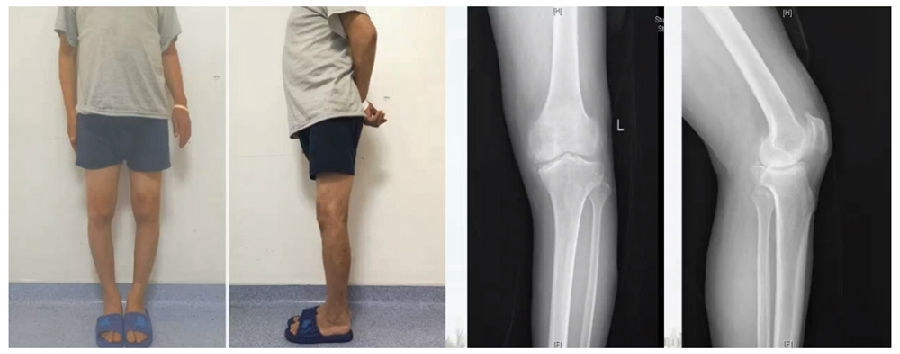

典型病例,男性,65岁,农民,双膝内翻16度。

术前影像

第一次为该患者做了传统上行开放截骨,撑开角度较大,术后用三种方法测量髌骨高度,发现髌骨高度受到影响,髌骨变低了。

左膝上行OWHTO(初次)

上行OWHTO髌骨高度测量

ISI法测量髌骨无明显变化;CDI、BPI法测量髌骨降低明显;患者屈膝锻炼困难。

第二次来院做另一侧肢体时,采用下行截骨,术后患者髌骨高度,无论用哪种方法测量都无明显变化,而且患者膝关节功能迅速得到恢复。

右膝下行OWHTO(再次)

下行OWHTO髌骨高度测量

ISI法测量髌骨无明显变化;CDI、BPI法测量髌骨无明显变化;患者屈膝明显改善。